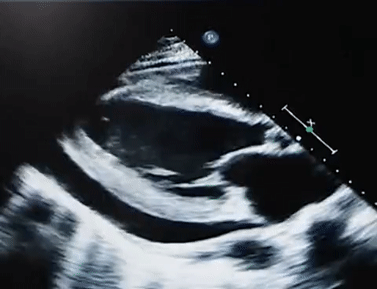

The images are examples of what cardiac pathology?

Constrictive Pericarditis

The image below is an example of what cardiac pathology:

Pericardial effusion

Constrictive Pericarditis with pericardial effusion

Acute pericardial effusion

Explain 2 findings in these images that support the diagnosis of constrictive pericarditis.